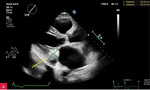

Rycina 3A-C. Badanie echokardiograficzne przezklatkowe (TTE) w osi krótkiej przymostkowej na różnych poziomach – płatków zastawki mitralnej (A), strun ścięgnistych (B) i mięśni brodawkowatych (C) – obrazuje owalną zmianę guzowatą, o dużych rozmiarach i nierównej echogeniczności, z widocznym wzmocnieniem brzeżnym